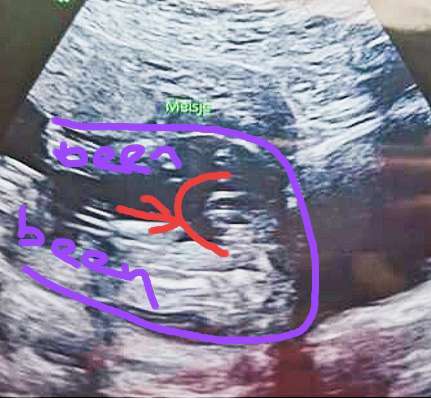

Is dit een 20-weken echo? Zijn die bij meer mensen zo onscherp? Want daar kunnen ze al die belangrijke details toch helemaal niet op zien? Bij ons zijn die echt veel scherper en die apparatuur was zelfs niet de beste vertelden ze.

Verder zou ik het wel bijzonder vinden als mensen hier op het forum aan een foto meer kunnen zien dan een opgeleide echoscopiste live op het scherm. Ze kijken zoveel belangrijke dingen na die amper te zien zijn, de kans dat ze het geslacht dan mis hebben is tegenwoordig echt heel klein (ik zeg niet dat het onmogelijk is, ik ken de verhalen 😉).

Maar.. om je vraag als leek te beantwoorden, ik zie ook een meisje voor zo ver ik er iets van kan zeggen ☺️

Ja, dit is een van de laaste foto's die ze gemaakt had. We vroegen nog om t geslacht, maar baby was erg druk en zij was vrij snel met foto maken. Rest was wel duidelijk gelukkig 😀

Maar dit is niet echt een antwoord op je vraag🙈 bij een meisje zou je 2 bobbeltjes moeten zien en bij een jongen 2 bobbeltjes met een puntje.